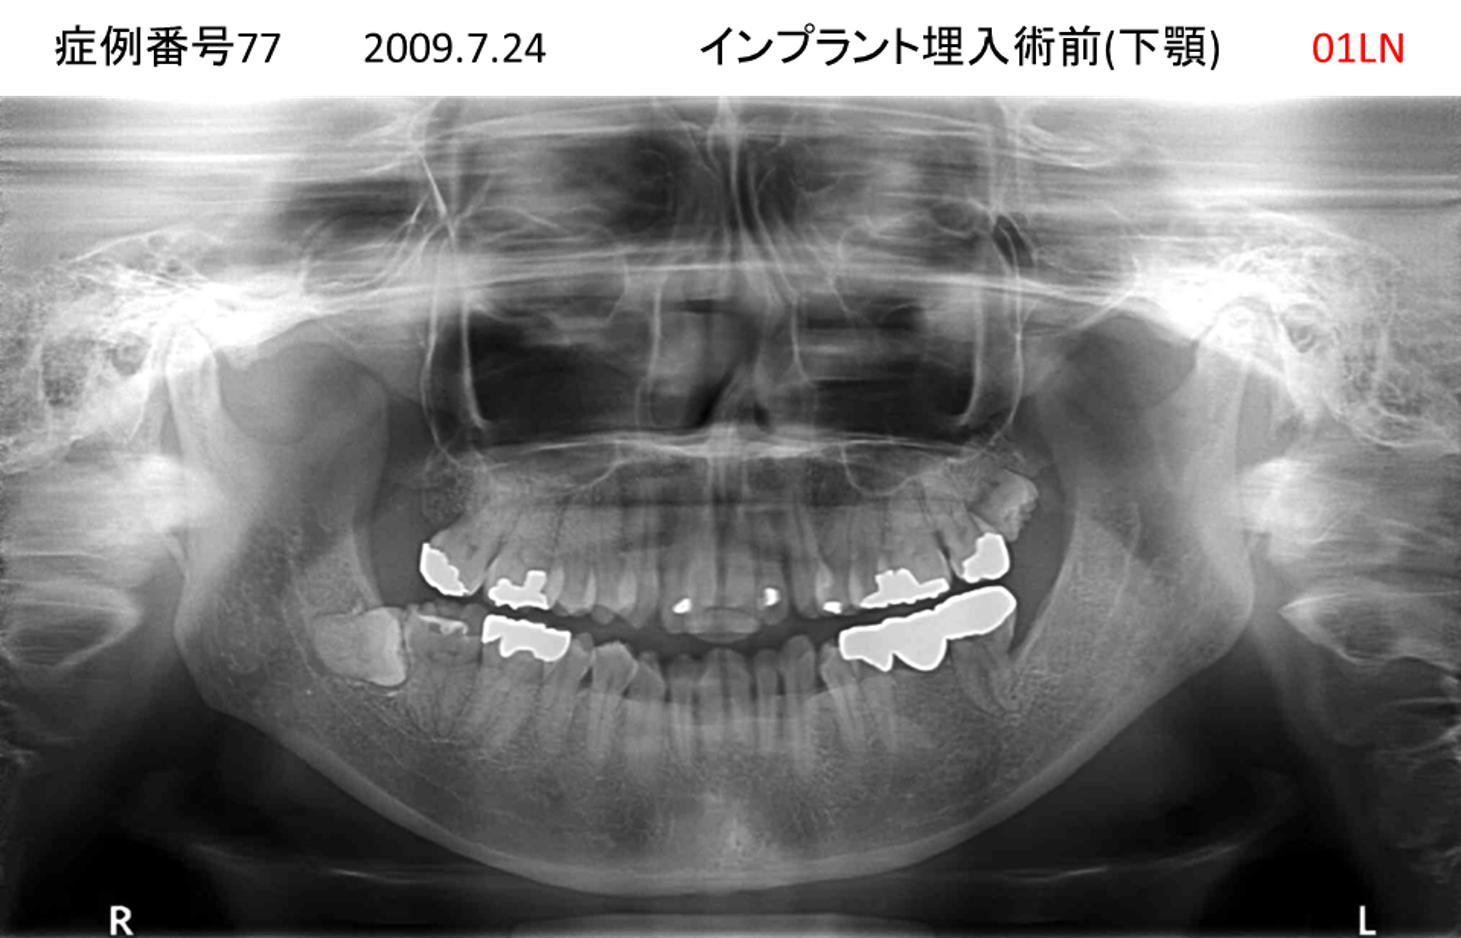

噛めない/固いものが食べられない患者様のインプラント症例

| 治療名称 |

インプラント |

| 治療費用 |

340万円+税 |

| 治療期間 |

6か月 |

| 患者さんの症状(主訴) |

噛めない。固いものが食べられない。 |

| 治療内容 |

サイナスリフト、抜歯即時インプラント |

| 治療結果 |

何でも食べられる。食事に困らない。 |

| 治療の注意点(リスク/副作用) |

インプラントが壊れたら再治療が必要 |